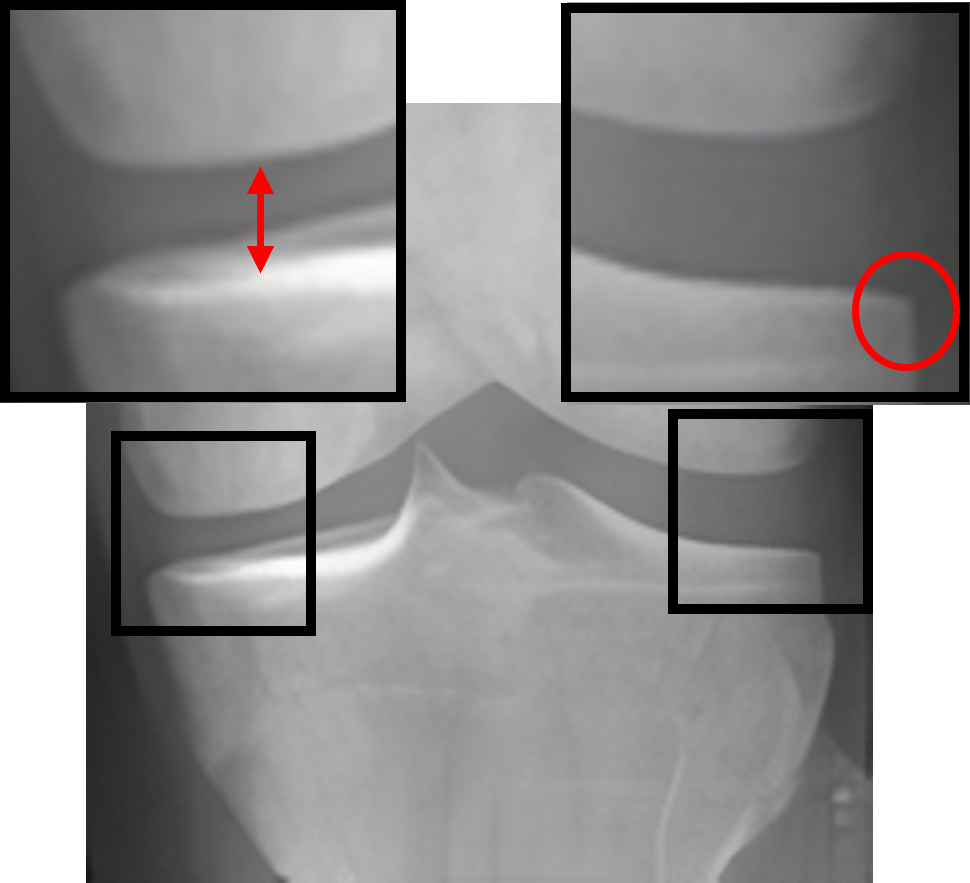

Table 2: Visualization of the synthesized intermediate frames

Input image Synthesized intermediate framessuperscriptSynthesized intermediate frames\stackrel{{\scriptstyle\text{Synthesized intermediate frames}}}{{\makebox[284.52756pt]{\rightarrowfill}}} Input image

xSsubscript𝑥𝑆x_{S} xS(φη=0.25)subscript𝑥𝑆subscript𝜑𝜂0.25x_{S}(\varphi_{\eta=0.25}) xS(φη=0.5)subscript𝑥𝑆subscript𝜑𝜂0.5x_{S}(\varphi_{\eta=0.5}) xS(φη=0.75)subscript𝑥𝑆subscript𝜑𝜂0.75x_{S}(\varphi_{\eta=0.75}) xTsubscript𝑥𝑇x_{T}

KL-0 KL-1∗∗ KL-2∗∗ KL-3∗∗ KL-4

[Uncaptioned image] [Uncaptioned image] [Uncaptioned image] [Uncaptioned image] [Uncaptioned image]

• *

The morphed areas of each frame were highlighted within black boxes, the red arrow and red circle indicate the locations of JSN and osteophyte formation, respectively. A shorter arrow indicates a smaller joint space (i.e., a narrower distance between the tibia and femur), while a larger circle indicates more osteophytes.

• **

The expected labels.

4.2 Visualization of the synthesized intermediate frames

In Table 2, we show the source image xSsubscript𝑥𝑆x_{S}, the target image xTsubscript𝑥𝑇x_{T}, and their intermediate frames (i.e., xS(φη=0.25)subscript𝑥𝑆subscript𝜑𝜂0.25x_{S}(\varphi_{\eta=0.25}), xS(φη=0.5)subscript𝑥𝑆subscript𝜑𝜂0.5x_{S}(\varphi_{\eta=0.5}) and xS(φη=0.75)subscript𝑥𝑆subscript𝜑𝜂0.75x_{S}(\varphi_{\eta=0.75})), which is crucial in understanding how the source images evolve into their registered state. The progressive alignment is quantified by the parameter η𝜂\eta evenly divided into 0.25, 0.5, and 0.75, which represents the extent of transformation at each stage of KOA, corresponding to KL-1, KL-2, and KL-3, respectively. As can be seen, xS(φη=0.25)subscript𝑥𝑆subscript𝜑𝜂0.25x_{S}(\varphi_{\eta=0.25}) shows the initial stage of the morphing process where the morphs are minimal and closely resemble the source image. For xS(φη=0.5)subscript𝑥𝑆subscript𝜑𝜂0.5x_{S}(\varphi_{\eta=0.5}), the morph is more pronounced, introducing clear signs of osteophytes and beginning to show a narrowing of the joint space. It is noteworthy that this frame is critical as it represents the halfway anchor point of the KOA temporal evolution process, showing a balanced mix of characteristics from both the source and target images. xS(φη=0.75)subscript𝑥𝑆subscript𝜑𝜂0.75x_{S}(\varphi_{\eta=0.75}) signifies an advanced stage of morph, introducing moderate multiple osteophytes, definite narrowing of the joint space, some sclerosis, and possible deformity of bone contour.